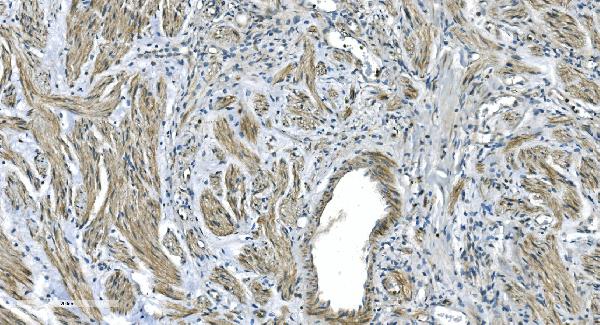

Periostin, Polyclonal Antibody (Cat# AAA19149)